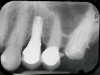

Fig 3. Fractured abutment screw.

Figure 3

Fig 4. Bending of the abutment prongs as a result of

motion caused by screw fracture.